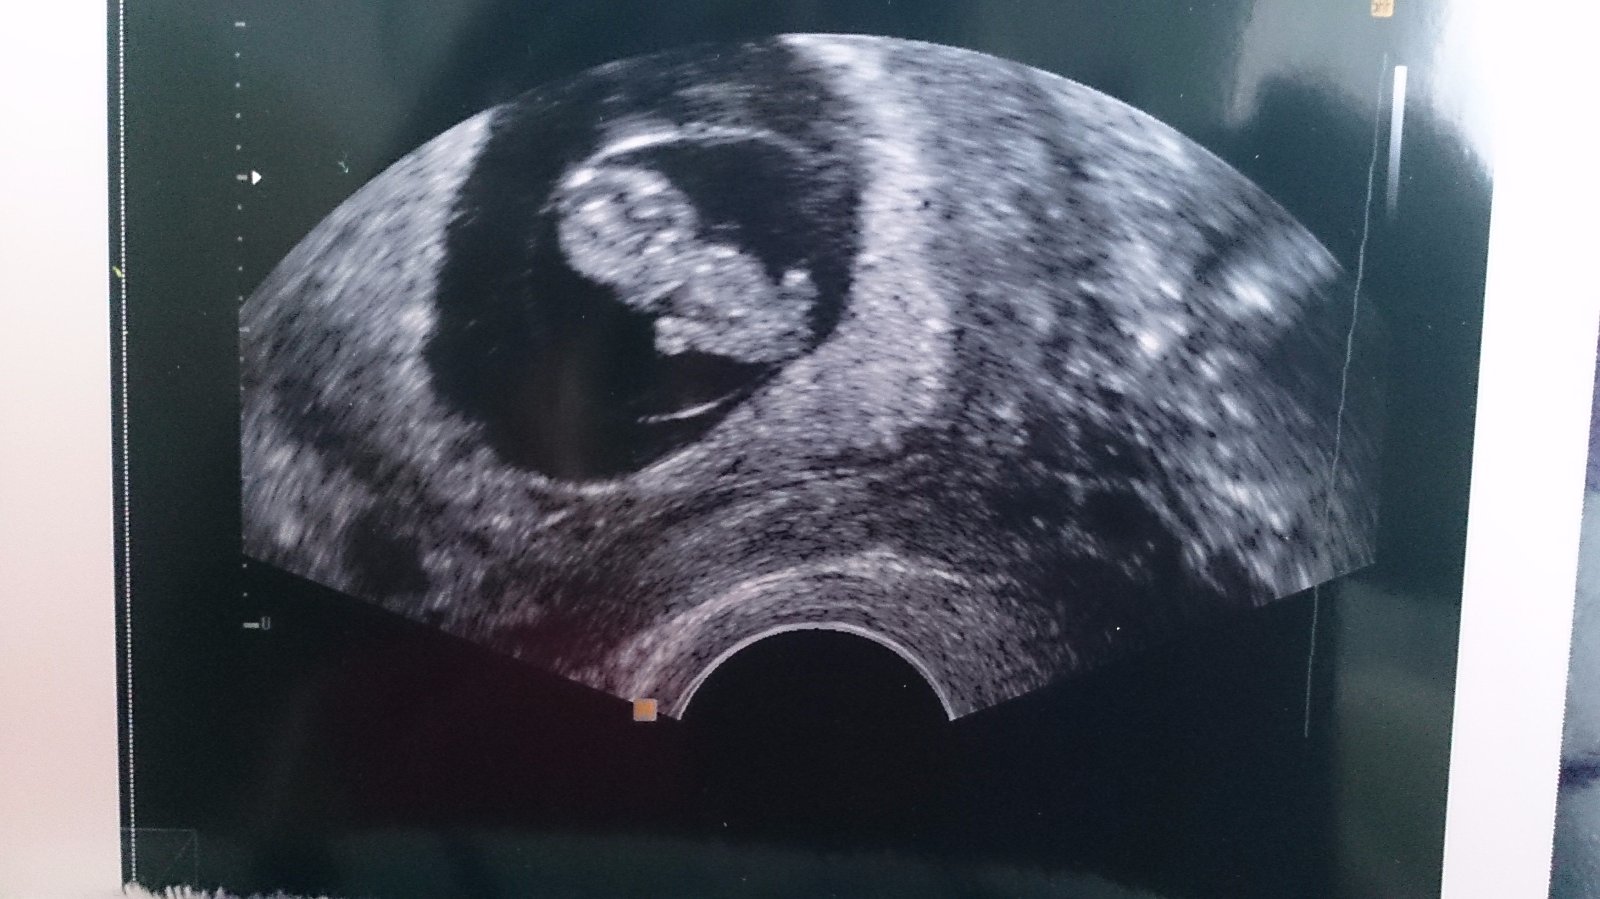

@briketaaaa Nadhera🙂